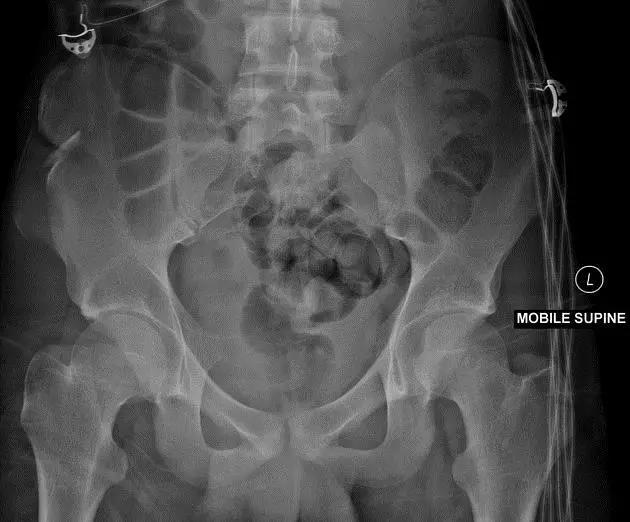

3. Straddle 骨折

双侧耻骨上下支骨折。

(来源:learning radiology)